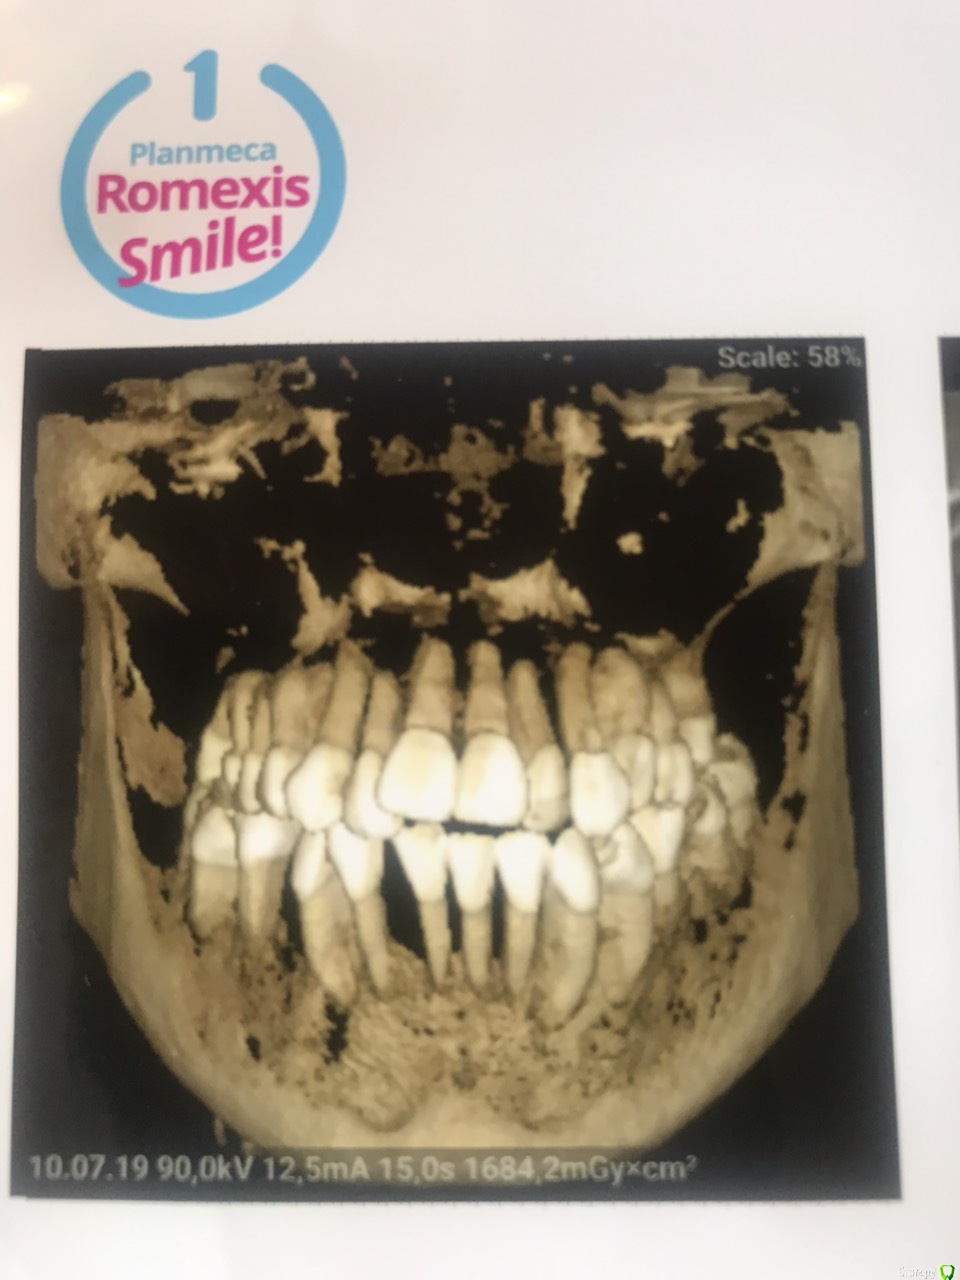

leyla-night Опубликовано 3 августа, 2019 Поделиться Опубликовано 3 августа, 2019 Добрый день! Очень нужен совет. Ходила в стоматологию к терапевту. сказали есть подвижность некоторых зубов. Сделали чистку. зубы стали остальные шататься, даже те которые не шатались, а один теперь болит, а я пришла у меня ничего не болела. Сказали сделать три Д снимок, сделала. Сообщили, что 7 зубов нужно удалять. Но заниматься мной не стали. Сказали, сами выпадут потом поставите челюсть. Я инвалид 1 группы не могу сидеть в кресле стоматолога. До 2013 года меня принимали в моей коляски и пломбы ставили и чистку делали все было нормально. Сейчас стоматологии стали еще лучше, но я не могу получить помощь. Посоветуете пожалуйста по моему снимку. можно, мне как то помочь., Ссылка на комментарий

hogsmeed Опубликовано 3 августа, 2019 Поделиться Опубликовано 3 августа, 2019 Здравствуйте Подвижность зубов после чистки обычное явление(вернее ощущение этой подвижности). По снимку действительно нужно убирать зубы, спасти их затруднительно, дальше либо имплантация, либо съемный протез). Принять пациента в коляске вообще не проблема, установки фирмы Adec например (довольно популярной фирмы) оборудованы подголовником, который позволяет лечить в вашем кресле. Ссылка на комментарий